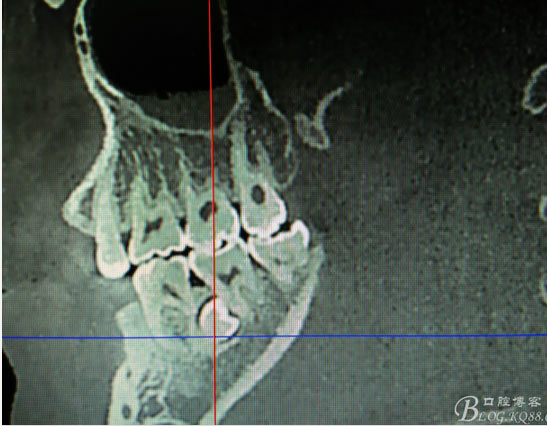

患者、盧xx、男、19歲。主訴:左側下頜乳磨牙未脫落,要求檢查。??茩z查:左側下頜第二乳磨牙有充填物。無松動,全景片檢查。35移位至36、37之間。頰舌側均不能觸及隆起。CBCT檢查:35位于36、37的舌側。表面骨質約2mm左右。35完全骨埋伏,36的遠中牙根疑是吸收。建議35暫觀察。置留不取。患者要求拔除擔心壓迫36牙根或者發(fā)生囊性變。術前簽手術同意書。

圖1.術前的全景片影像檢查,35移位至36、37之間。